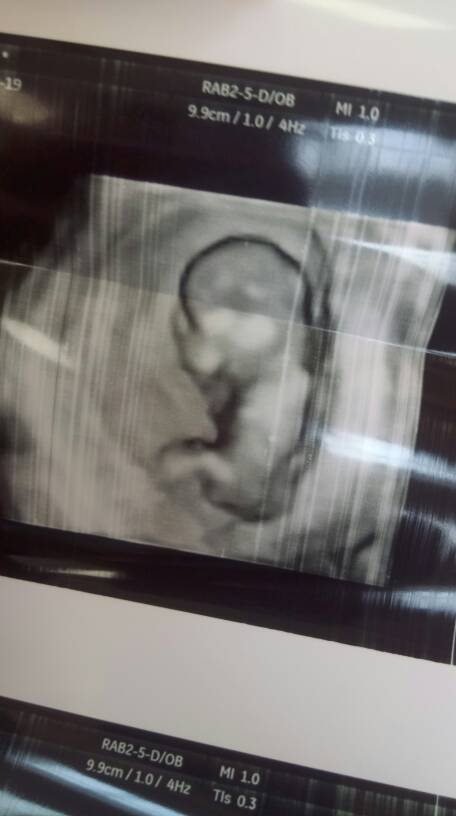

Kochane, oto mój zdrowy maluszek [emoji7] nie chciał współpracować, ruszal sie energicznie, machal do nas rączkami i nozkami, ale udalo sie pomierzyc co bylo trzeba [emoji7] nie pokazal czy jest chlopcem czy dziewczynka [emoji4] mąż wzruszony, mowi ciagle o tym, ze widzial jak kopie [emoji16] słyszeliśmy tez serduszko, ktore bije w tempie 164 [emoji173] pan doktor powiedzial ze dzieciątko lubi sie do mnie przytulac, bo ciagle wtulone w tyle [emoji4] moje 7,7cm miłości [emoji173]Zobacz załącznik 876836